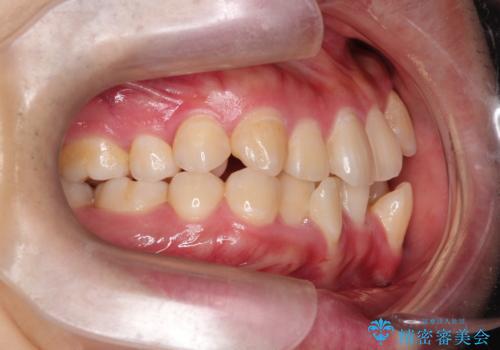

上下左右小臼歯を抜歯する治療計画を立て審美装置にて治療を行いました。

骨格的3級傾向もあり、咬合関係を仕上げるのに時間がかかりましたが、患者様には大変満足していただけました。

難しいケースでしたが、矯正用アンカースクリューを用いながら、臼歯関係もきれいに仕上げることができました。